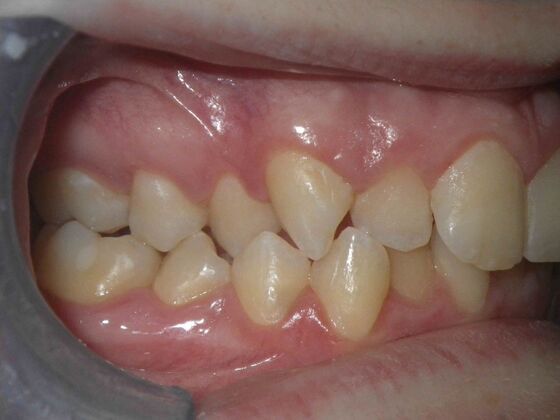

Orthodontics: Case 4

Description

Patient presents with constricted upper and lower arches, numerous crossbites on right side, with upright central incisors on upper arch that will need to be flaired to provide adequate lip support. I decided to use on this case self ligating brackets, to help with expansion purposes. This case turned out very well with flairing of upper centrals, crossbite corrections, expansion of arches, as well as establishing better arch form and symmetry.